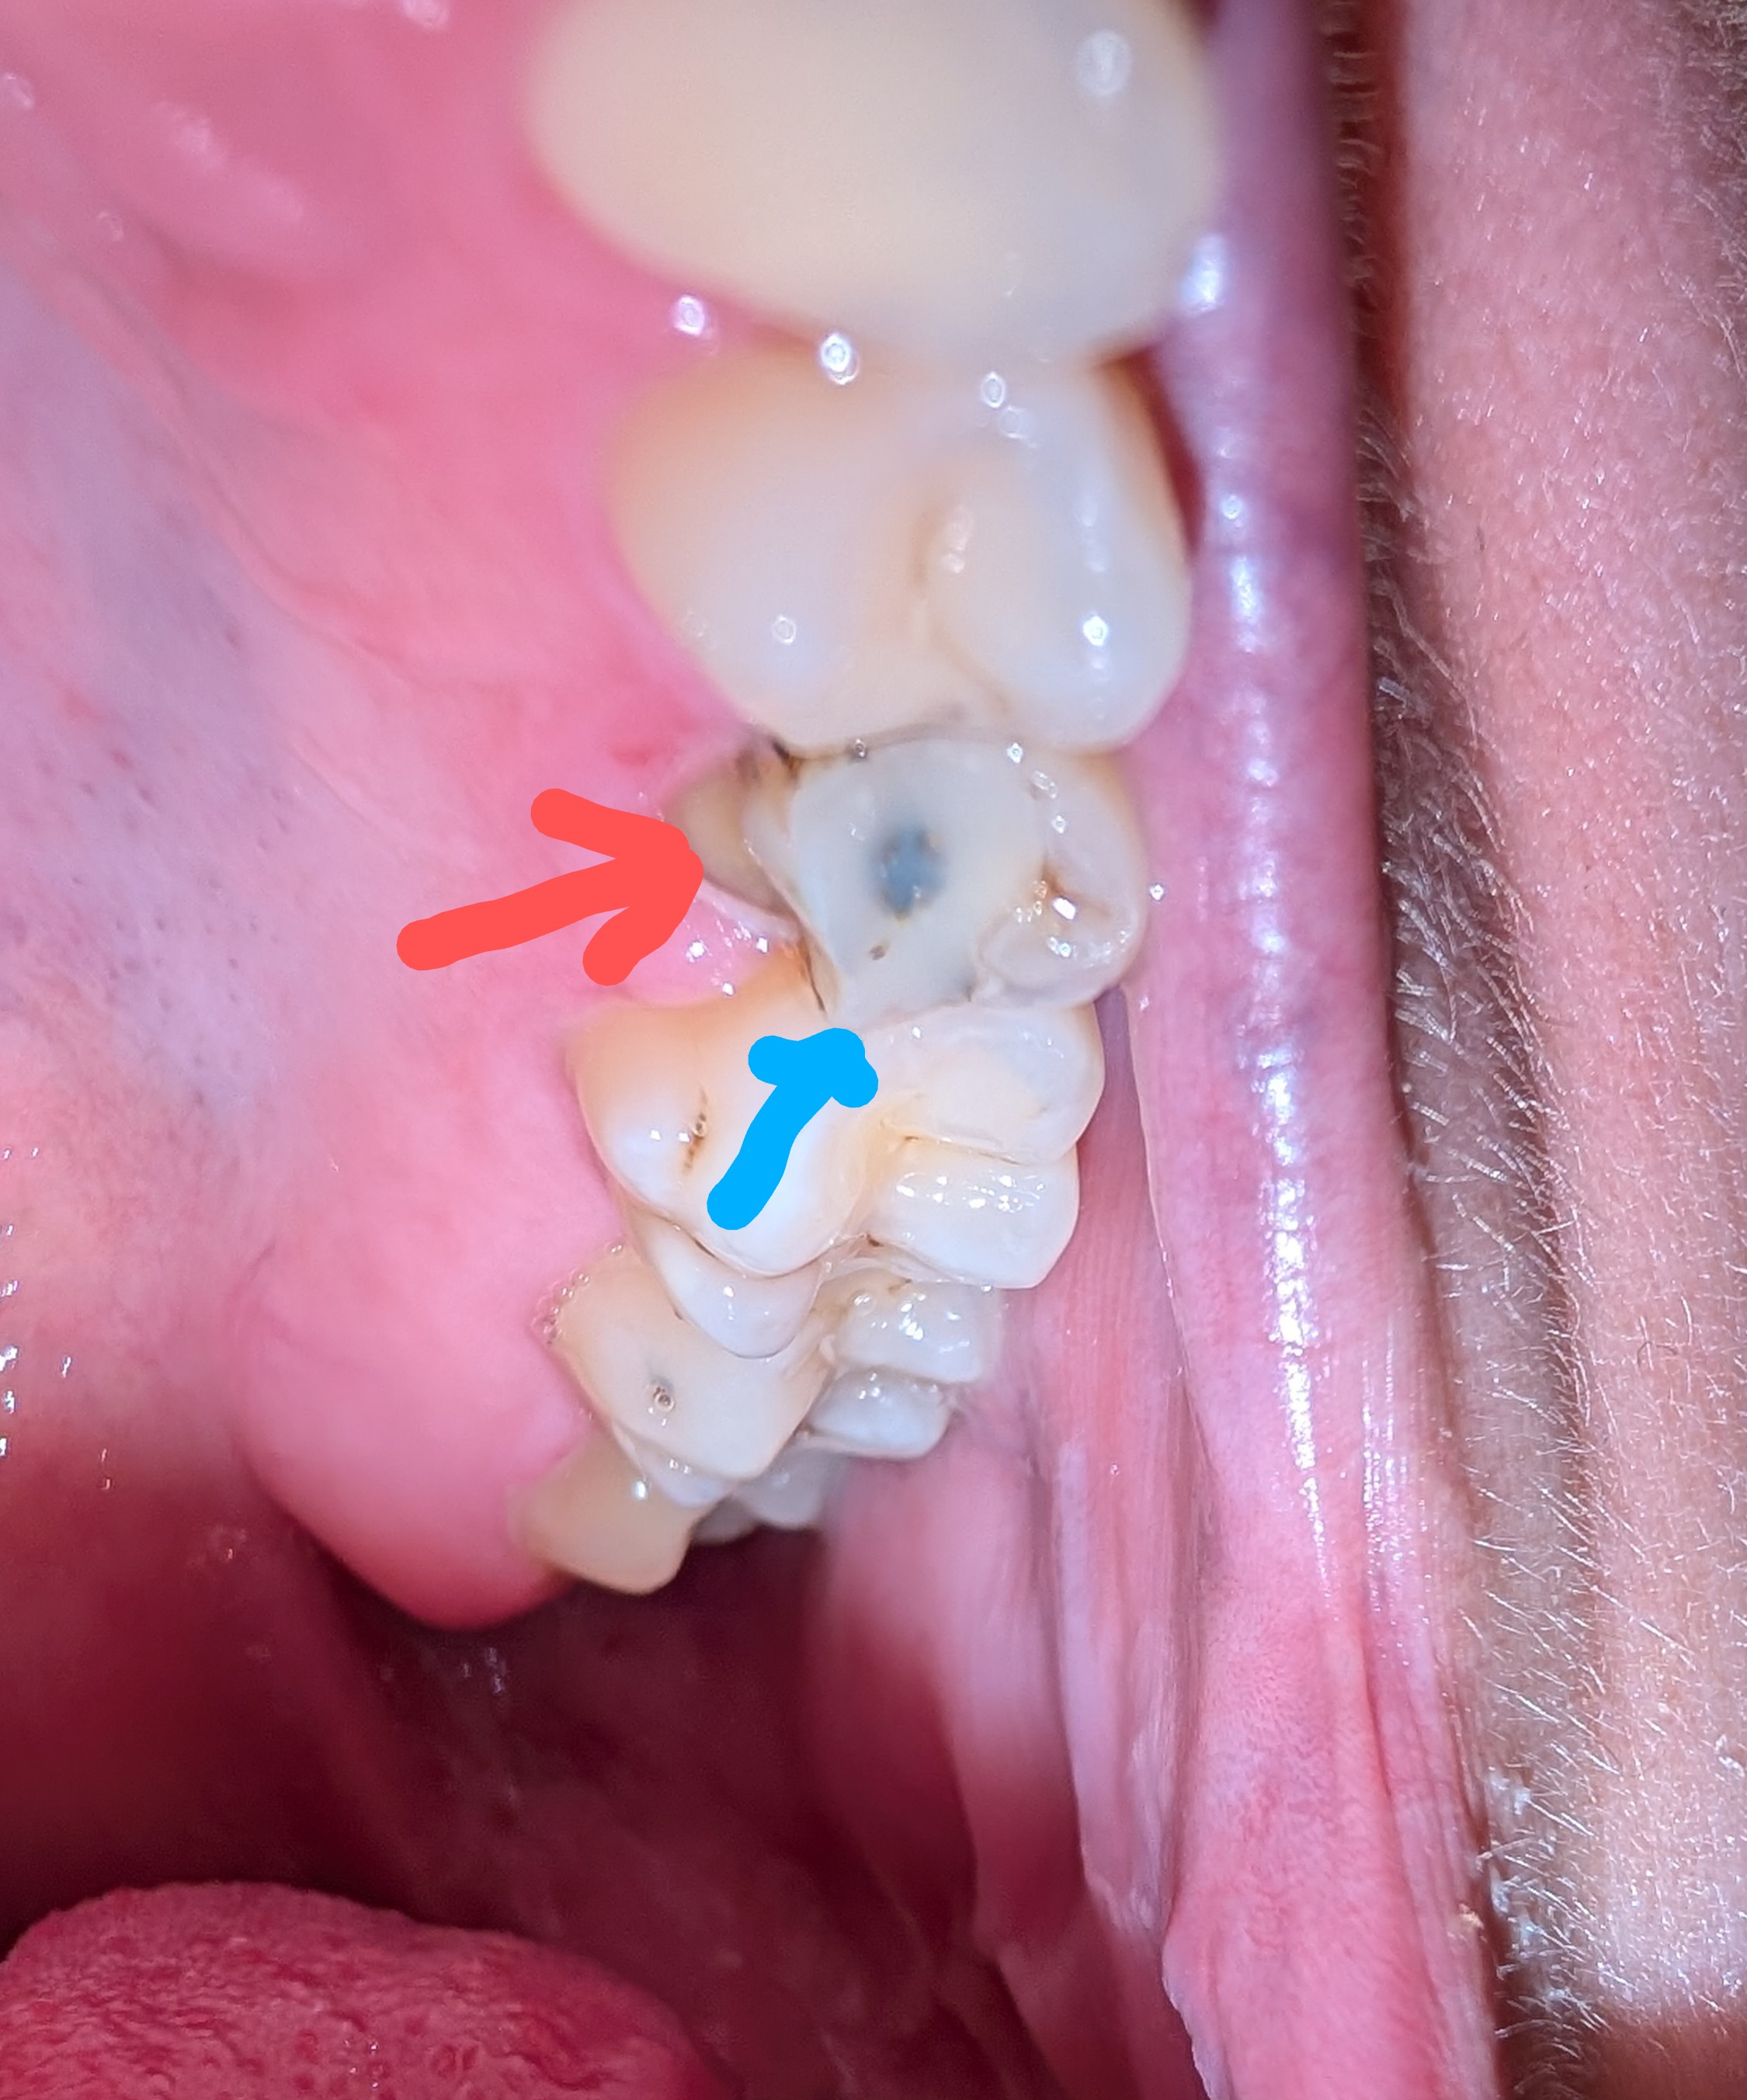

Zul je net zien dat ik vandaag (op een vrijdag om 17:00 notabene) op iets hards bijt in mijn eten en mijn halve kies afbrak aan de wang kant. Nu is er dus paniek in de tent! Ik ben meteen aan het lezen geslagen en heb begrepen dat een kies die tot het tandvlees afgebroken is (rode pijl op de foto) niet gered kan worden en dus getrokken zal moeten worden. De blauwe pijl geeft de vulling aan. Dit is echt mijn aller, aller grootste angst en mijn hele weekend is hierdoor verpest, ik heb nu al kriebels in mijn buik en weet zeker dat ik ga dromen vannacht.